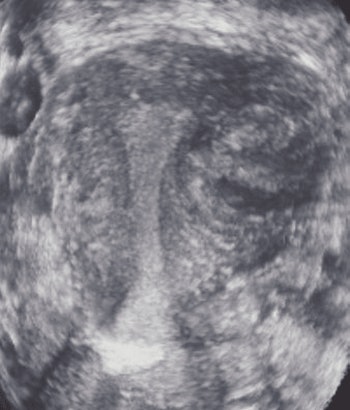

![]() |

| A 40-year-old woman with a fibroid. Above, transverse view of uterus shows fibroid (calipers). Exact location of fibroid with respect to uterine cavity is unclear because posterior aspect of fibroid obscures side of endometrium. Below, coronal view shows that fibroid is not submucous, but is intramural without distorting shape of uterine cavity. Plane shown here was deemed by radiologist to be best plane to show closest relationship between fibroid and endometrium, showing that the fibroid did not extend into cavity but just abuts it. Benacerraf B, Shipp T, Bromely B, "Which Patients Benefit from a 3D Reconstructed Coronal View of the Uterus Added to Standard Routine 2D Pelvic Sonography?" (AJR 2008; 190:626-629). |